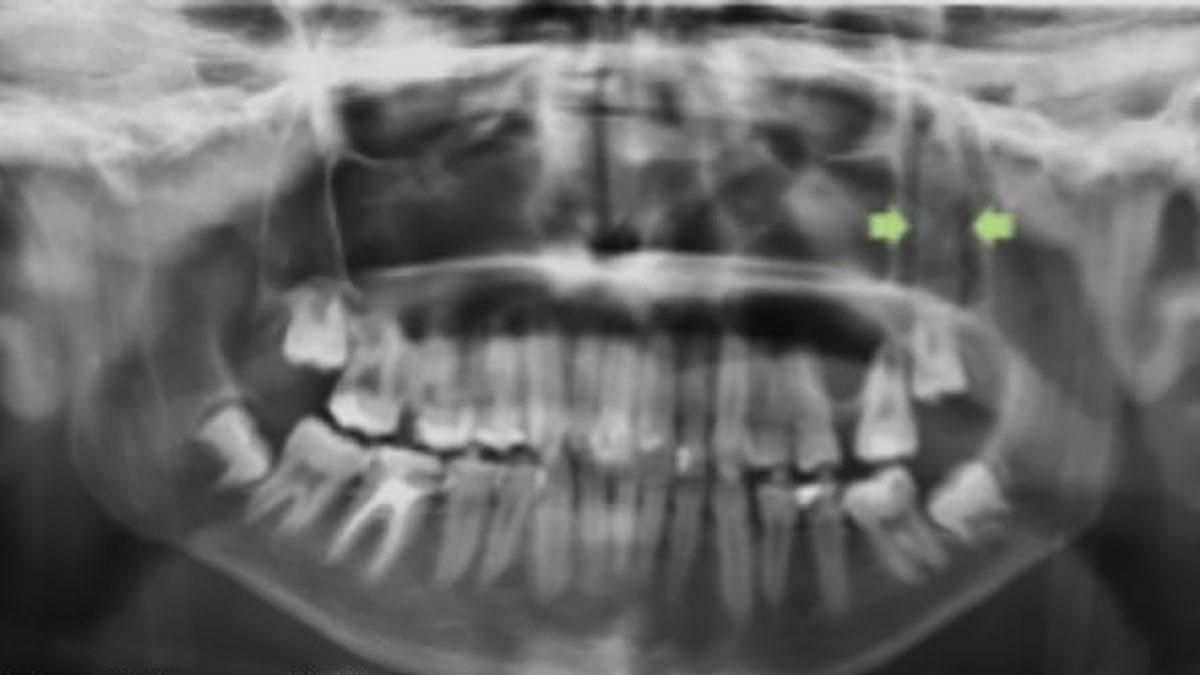

Лікарі Університетської лікарні "Вірген-дель-Росіо" в іспанській Севільї зробили рентген щелепи і виявили, що під вилицею щось "ховається". Також хлопець пройшов комп'ютерну томографію. Вона підтвердила, що за щокою є сторонній предмет, який має форму ножа.

Скло застрягло під вилицею: фото

Медики зазначають, що такий випадок відносно рідкісне явище, оскільки ділянка обличчя, куди проникло чужорідне тіло, добре захищена вилицею.

Хірурги провели операцію і витягли предмет, який насправді був не ножем, а уламком скла, через рот підлітка.

Скло, яке дістали хірурги з щелепи хлопця